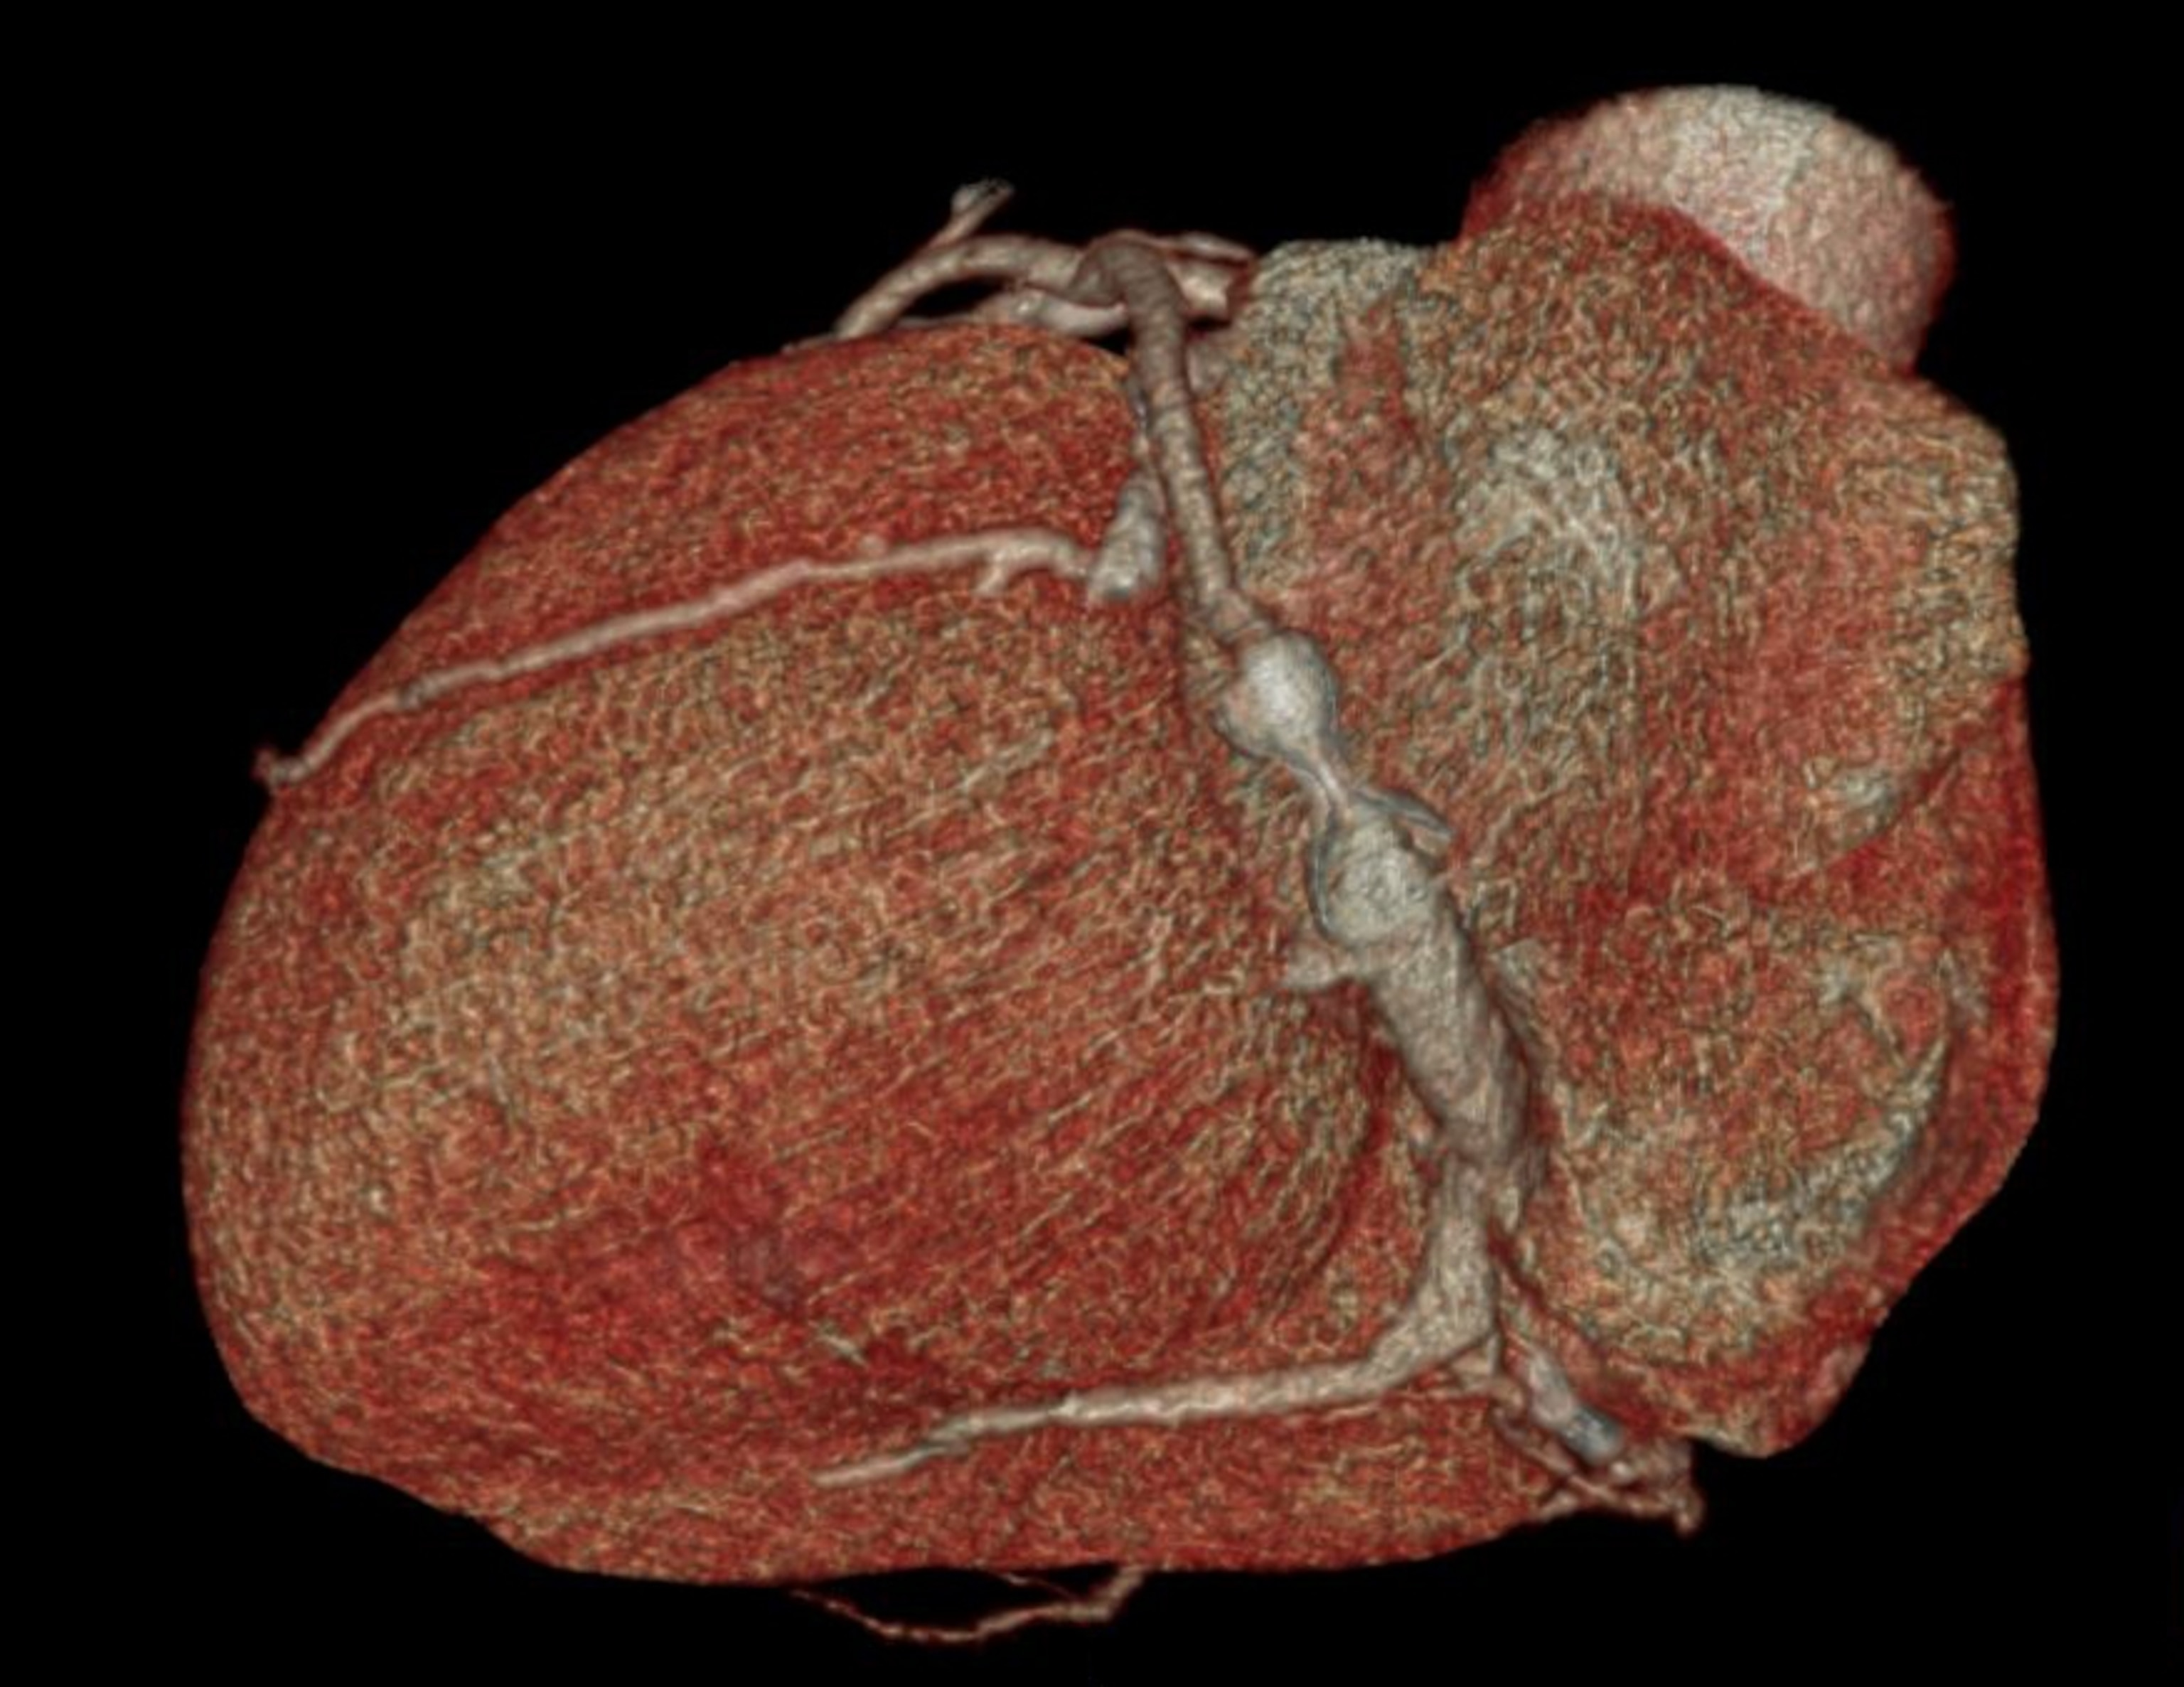

Our perception of pain isn’t limited to merely sensing it. The feelings of unpleasantness, fear, and anxiety that accompany the sensation are an integral part of experiencing pain. In a trial at the Cleveland Clinic, researchers led by neurosurgeon Andre Machado used deep brain stimulation (DBS) to target this emotional component of pain in 10 patients who had chronic neuropathic pain after suffering a stroke. The researchers implanted tiny electrodes in a part of the brain involved in processing emotions. Wired to an electronic device inserted in the chest, the electrodes delivered mild shocks to the implantation site at a rate of nearly 200 a second.

A subsequent part of the study involving both healthy subjects and chronic pain patients gave Machado and his colleagues some insight into why deep brain stimulation appeared to have benefited patients like Grubb. The researchers recorded electrical activity from the brains of participants as they watched a screen while they had two devices strapped to their arms. One device delivered a flash of heat to the skin; the other delivered a harmless buzz. From the visual cue that appeared on the screen, the participants could tell which of the two stimuli they were about to get or if they were going to get nothing at all.

The researchers compared the brain activity of participants as they received heat pulses and buzzes or nothing. They found that the brains of chronic pain patients responded similarly when anticipating a painful stimulus and a harmless one, whereas the brains of healthy volunteers showed increased activity in certain regions only when anticipating the heat. When chronic pain patients repeated the experiment while receiving DBS, their brain activity was more similar to that in healthy participants.

To Machado and his colleagues, these findings suggest that the brains of chronic pain patients are conditioned by constant exposure to pain to react as if every stimulus is potentially painful, causing the patients to live in distress. The DBS treatment seems to restore a degree of normalcy, enabling the brain “to again distinguish painful from nonpainful, which is what you need in order to be able to function,” Machado says.